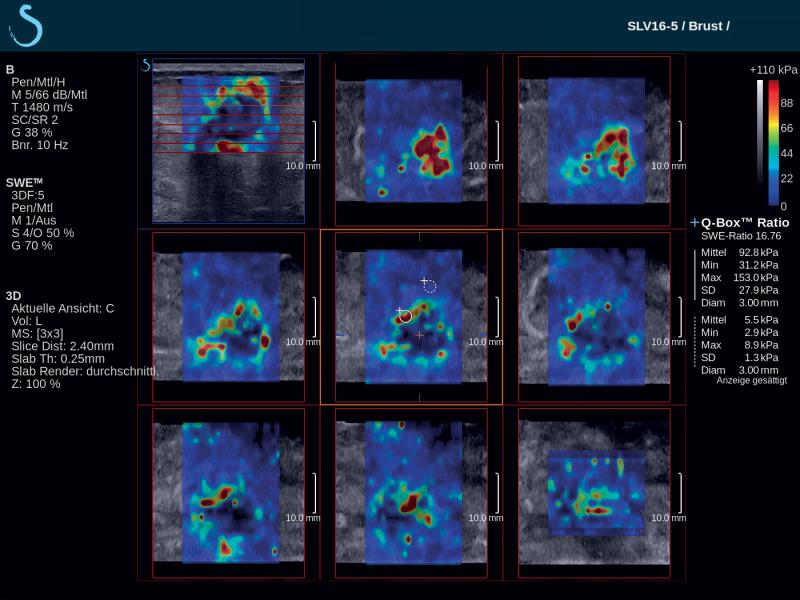

French-based ultrasound company Supersonic Imagine introduced the Aixplorer Mach 30 with Shear Wave Elastography (SWE) Plus functionality, which it highlighted at the 2019 Society of Breast Imaging/American College of Radiology (SBI/ACR) symposium in April. Shear wave elastography is a technique that measures the stiffness of tissue with ultrasound waves; this can provide important diagnostic information about the organ or structure in question. In breast imaging, the technique can help distinguish whether a mammary lesion is benign or malignant. SWE Plus on the Aixplorer Mach 30, which SuperSonic Imagine bills as the next generation of the technology, offers greater performance of real-time, reliable, quantitative and reproducible evaluation of tissue stiffness and visualization. It offers greater diagnostic precision, which considerably reduces the number of false positives and unnecessary biopsies.